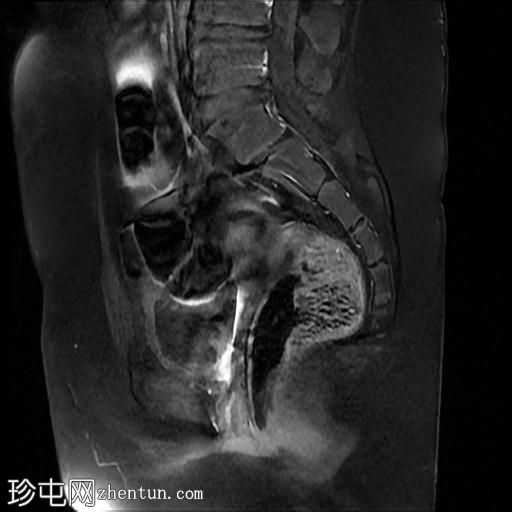

矢状面

T2

MRI序列显示:

女性外生殖器

子宫、宫颈及阴道上2/3缺失

左侧睾丸及腹股沟管内环

右侧睾丸位于腹腔内,靠近腰大肌

双侧卵巢未显影

MRI结果提示雄激素不敏感综合征 (AIS),患者基因构成为男性,但外生殖器为女性(46XY核型)。由于细胞对睾酮等雄激素产生抵抗,雄激素不敏感综合征常伴有双侧隐睾。